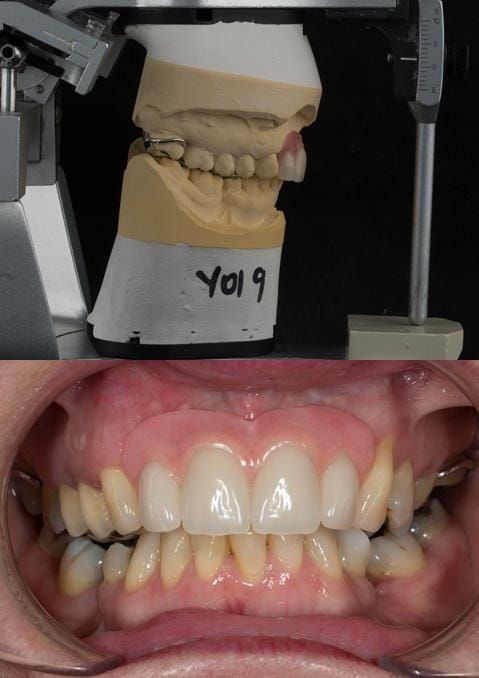

Provision of a maxillary cobalt chromium based partial denture/protective occlusal splint in a heavily restored dentition

- Extract the upper 2-2 teeth and replace with an interim acrylic based partial denture. Reline the interim denture over 9 - 12 months, replacing with a definitive cobalt chromium based partial denture. The definitive denture would ideally be designed as an occlusal protective splint to reduce the the potential for mechanical wear and breakages of the moderately/heavily restored maxillary dentition. In addition, should further upper teeth require extraction they could be added on to the denture cobalt chromium framework - therefore a new prosthesis would not be required as future teeth are lost. This option would produce an excellent aesthetic outcome. This is the option the patient chose to have.

Following consultation and second discussion appointment the patient chose to have option 3 namely, a maxillary cobalt chromium based partial denture/protective occlusal splint. The clinical situation and treatment process is shown in detail below with photographs. The patient was successfully rehabilitated with this and her quality of life considerably improved. The clinical work was provided by Finlay and the technical work by Rowan.